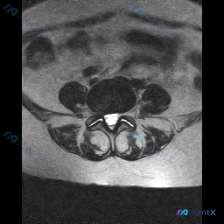

刚整理了一份很有警示意义的读片病例,分享给大家,这个坑平时读片真的很容易踩。 病例基本信息 临床诉求:患者因腰痛就诊,临床怀疑椎间盘病变,提供一张腰椎MRI T2加权轴位影像请读片。 影像基础评估 这是一张腰椎横断面(轴位)T2加权影像,清晰度和信噪比都不错,没有明显运动伪影,可以清楚辨认椎体、椎弓...

刚整理了一份腰椎MRI读片病例,只有单张轴位T2加权图像,把完整的分析思路整理出来和大家分享。 一、影像基本信息 这是一张腰椎MRI轴位T2加权图像,清晰度良好,解剖结构辨识度高: - 扫描水平为腰椎单个节段(大概率L4/5或L5/S1,具体需结合矢状位确认) - T2序列特征符合典型表现:脑脊液高...

看到这张腰椎MRI轴位的椎间盘病例,整理了完整的读片和分析思路,和大家一起讨论。 一、病例影像基本信息 这是腰椎MRI T2序列的轴位影像,层面位于下腰椎水平,可清晰显示椎体、椎间盘、椎管及周围软组织结构: 1. 核心异常信号:椎间盘髓核信号明显减低,呈中等偏低信号,不符合正常髓核的高信号表现,提示...

刚整理完一份腰椎MRI轴位片的读片分析,针对椎间盘病变的问题把完整思路梳理出来,和大家一起讨论。 病例影像基础信息 这是一份腰椎MRI T2序列轴位图像,临床问题是评估椎间盘病变,以下是影像可见的核心表现: 1. 椎间盘:该节段髓核T2信号明显减低,呈均匀低信号,也就是我们常说的「黑间盘」,提示椎间...

看到这一份腰椎MRI读片病例,临床怀疑存在椎间盘病变,我们整理一下影像资料和完整分析思路,大家一起讨论。 病例影像资料 本次提供的是腰椎MRI T2序列轴位图像,分析如下: 1. 扫描层面:位于下腰椎节段,可清晰辨认中央的硬膜囊、马尾神经根,以及侧方的关节突关节、椎旁肌肉 2. 核心影像发现: -...

收到一份腰椎MRI单张轴位片,临床怀疑椎间盘病变,整理一下读片思路和分析,和大家交流。 一、影像基本信息 这是一张腰椎MRI T2加权轴位扫描图像,我们逐层拆解结构: 1. 椎体与终板:椎体后缘信号正常,低信号符合皮质骨表现,没有明显骨质破坏、水肿,也没有典型Modic终板炎改变 2. 椎间盘:髓核...